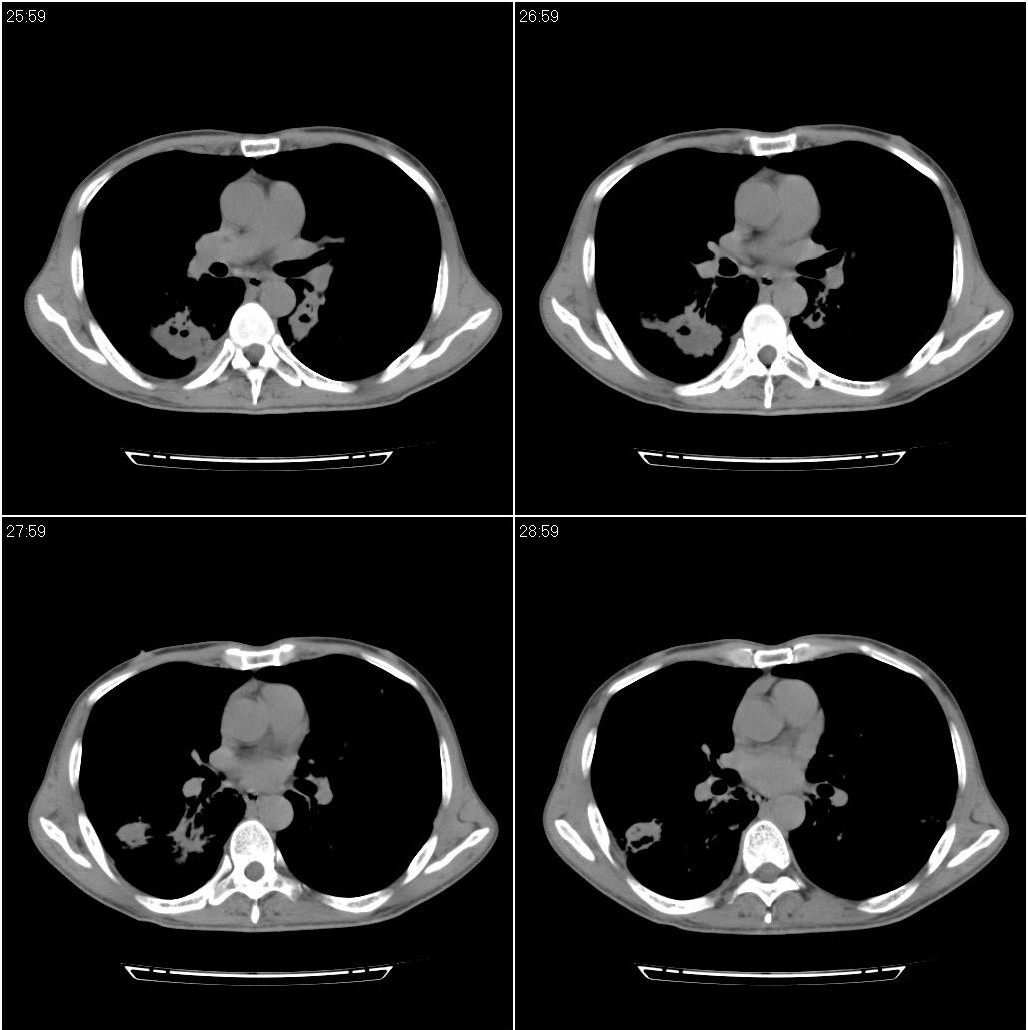

标题: CT23980:男性,47岁。近来咳痰、咳血,血沉增快(40左右),

男性,47岁。近来咳痰、咳血,血沉增快(40左右),痰中未检出结核杆菌。

两肺继发性肺结核并多发性结核球形成,部分病灶内空洞形成。

符合继发性结核表现部分空洞形成并播散